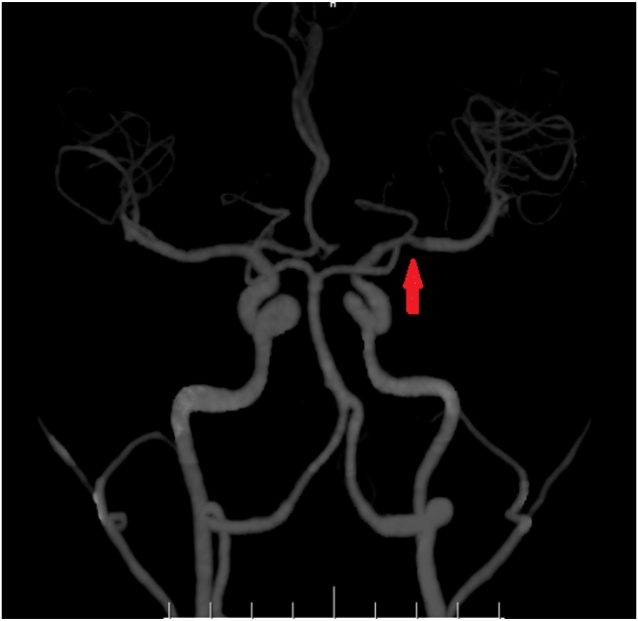

CTA提示:左侧大脑中动脉M1段节段性狭窄。

“检查发现患者大脑左侧多发梗死灶,影响了对侧肢体的支配能力及语言功能。”结合患者的症状和相关检查结果,该院神经内二科主任钟水生诊断其为脑梗死。